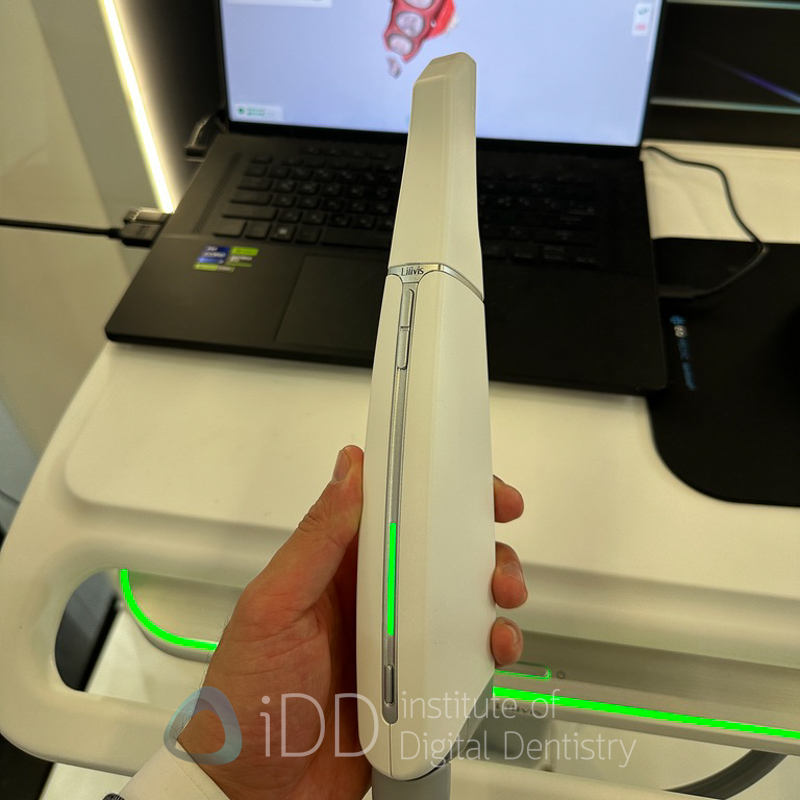

Lilivis - OCT Scanning Technology

Lilivis delivered one of the most surprising innovations at IDS 2025 with the unveiling of their prototype OCTIX scanner, which utilizes Optical Coherence Tomography (OCT) technology rather than conventional intraoral scanning methods.

Unlike traditional intraoral scanners that capture only surface data, this approach enables visualization through tissues - reportedly up to 0.5-1mm through enamel and through gingival margins. This capability could transform restorative dentistry by allowing clinicians to see subgingival margins, detect early caries beneath seemingly intact enamel, and allow for the measurement of enamel thickness.

Although it is a prototype for now, and when I tried it, it was quite slow, it is a fascinating approach to intraoral scanning. I will be watching this closely to see how it develops over the years. This technology represents a potentially disruptive advancement in digital impression technology.

If Lilivis can successfully bring this product to market with the capabilities demonstrated, it could address some of the most persistent issues clinicians have with digital impressions - particularly visualization of deep subgingival margins and detection of conditions beneath intact tooth surfaces.